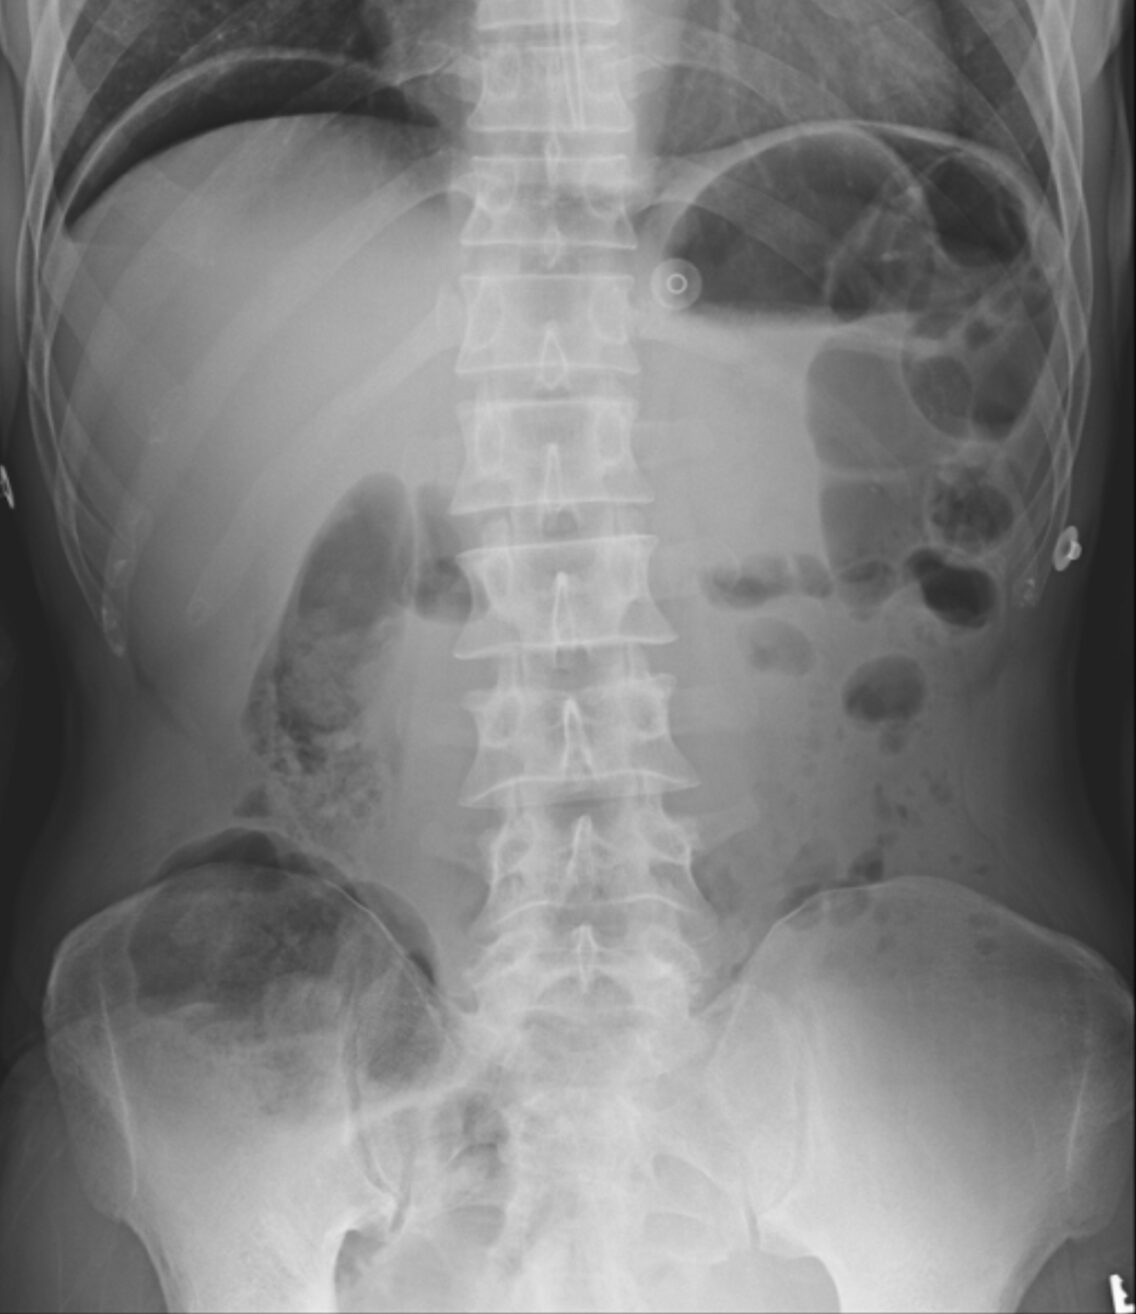

Chest X-Ray (CXR):

- Advantages of upright CXR:

- Can be done at the bedside for the unstable patient.

- Quick/convenient.

- Immediately available for review.

- Presence of pneumoperitoneum is diagnostic for a perforated viscus in 85-90% of cases.23,24

- Limitations:

- Variable sensitivity:

- Only 50-70% of hollow visceral perforations present with the characteristic ‘air under the diaphragm’ on an upright CXR, dropping as low as 20% in some studies.23,24

- Diagnostic utility is significantly limited by technique/positioning.

- Does not indicate the location of the perforation.23

Figure 1. Free air under the right hemidiaphragm on upright CXR, caused by bowel perforation. Source: Kulkarni R, Bowel perforation – subdiaphragmatic free gas. Case study, Radiopaedia.org (Accessed on 09 Nov 2025) https://doi.org/10.53347/rID-21444

A 55-year-old man with a history of peptic ulcer disease presents to the ED with sudden, severe abdominal pain that began abruptly around 12 hours ago. He describes the pain as intense and constant, radiating to his shoulders. He also reports feeling nauseated but has not vomited. On examination, he has significant abdominal tenderness with guarding and rigidity. His vital signs show mild tachycardia. His X-ray is shown above. What is the most appropriate next step?

This patient’s presentation, including the acute onset of severe abdominal pain, radiating shoulder pain, abdominal rigidity, and the presence of free air under the diaphragm on X-ray, strongly suggests perforated peptic ulcer disease (PUD), and the most appropriate next step in this scenario is surgical consultation.

Diagnosis of a perforated peptic ulcer is typically made with imaging. An upright chest or abdominal X-ray often reveals free air under the diaphragm, confirming the presence of a perforation. If the diagnosis is uncertain or if additional anatomical detail is needed, a CT scan of the abdomen can provide a more detailed view of the perforation and extent of intra-abdominal air and fluid. Laboratory tests may show leukocytosis and elevated inflammatory markers, though these findings are nonspecific. Serum amylase may be mildly elevated, especially in cases that involve gastric perforation.